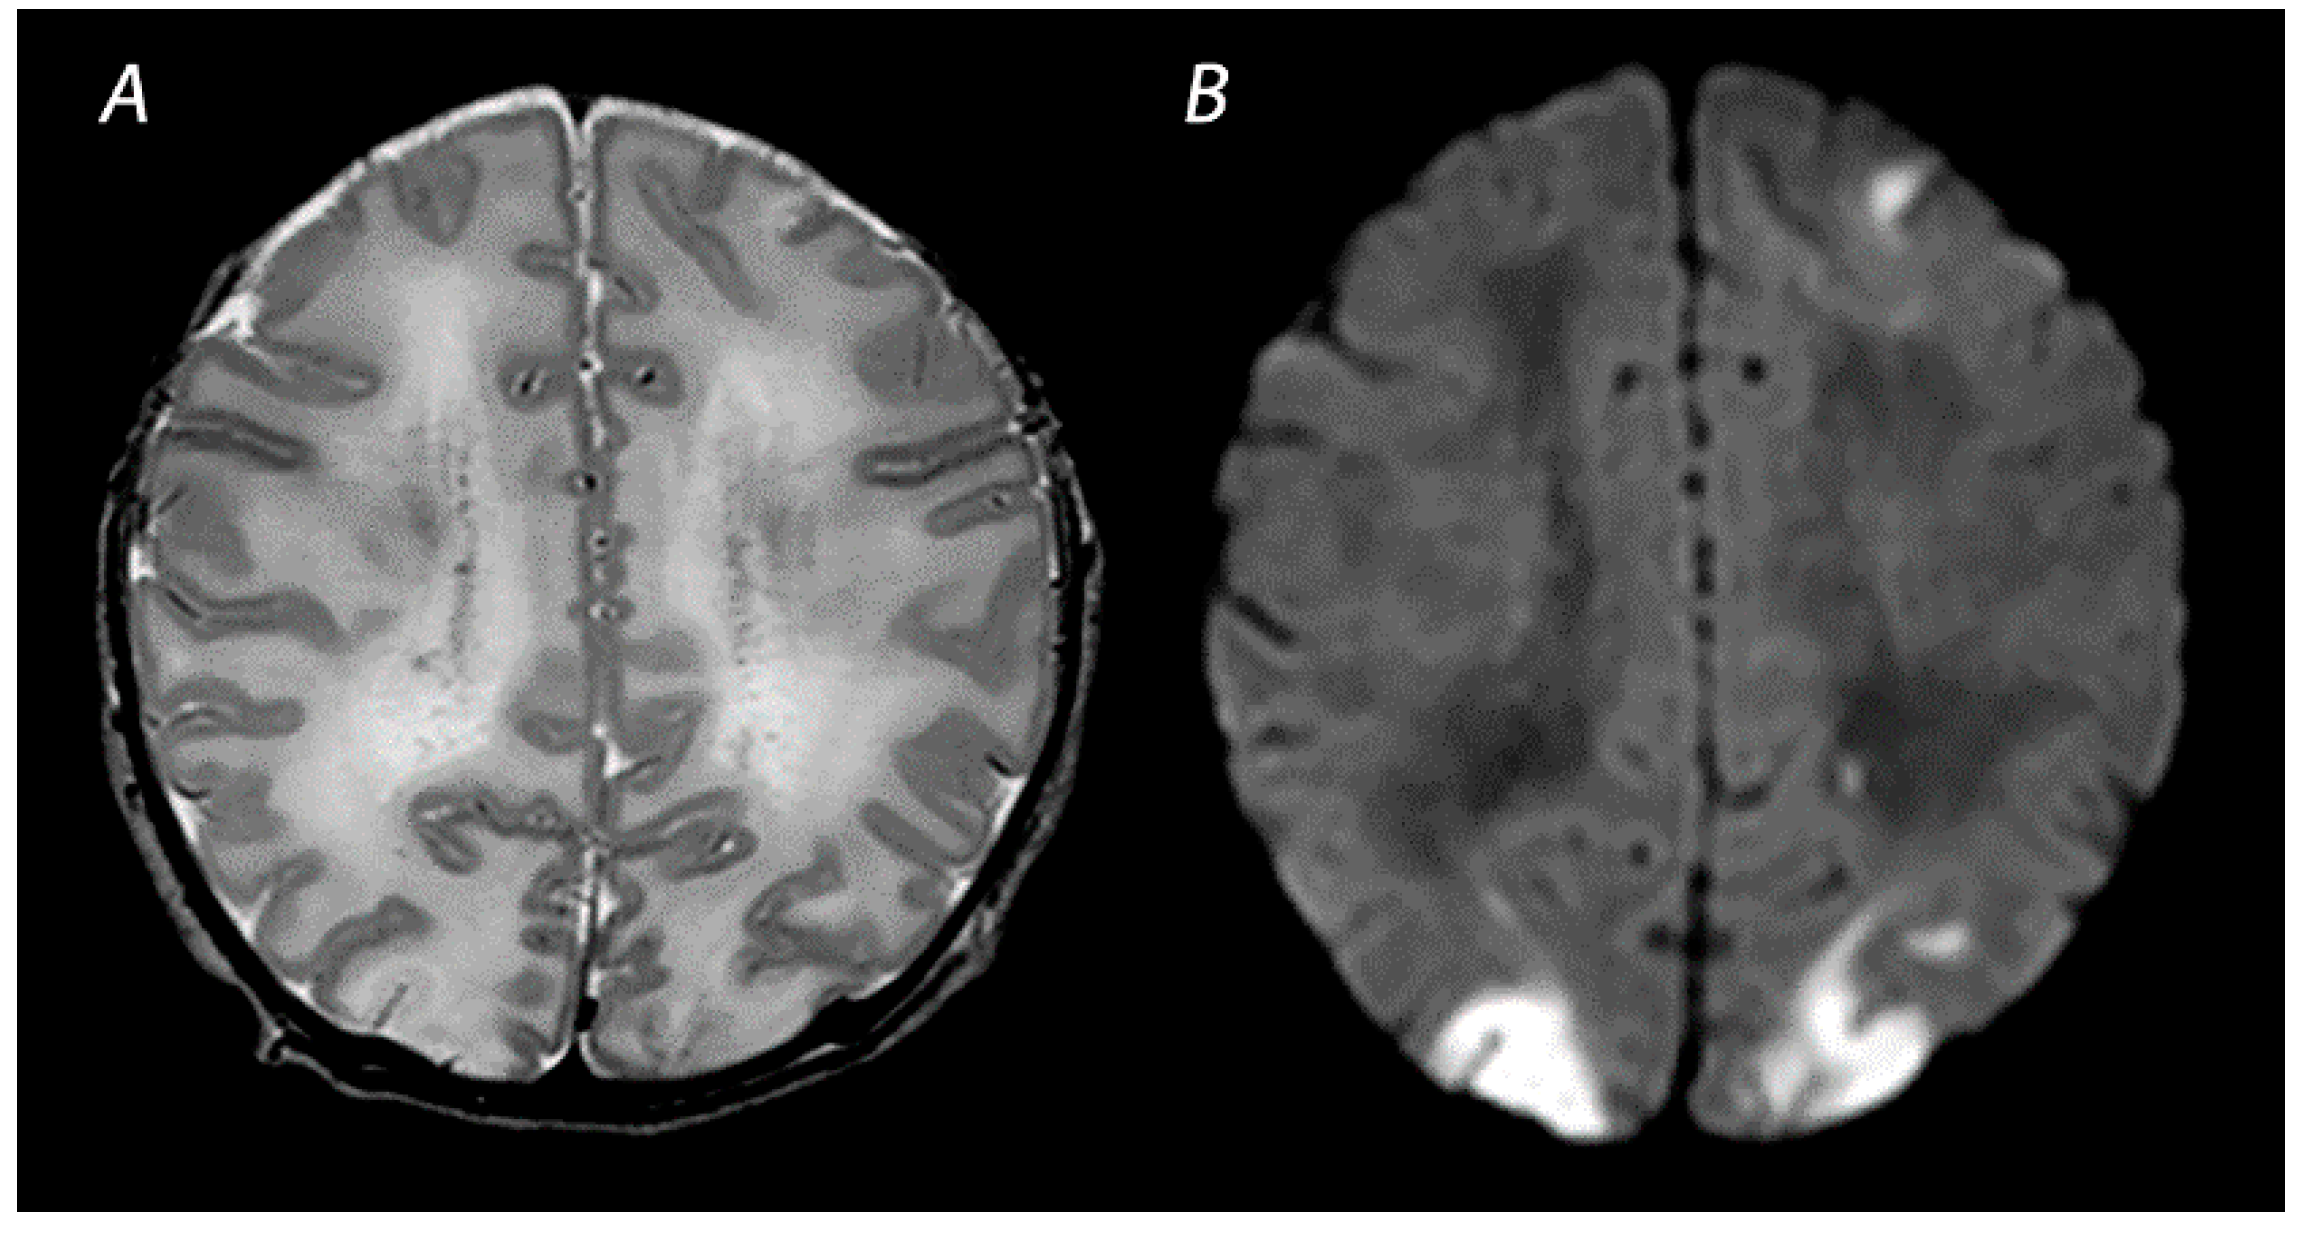

2.2. White Matter/Watershed (WM/WS) Predominant Pattern of Injury

| WM/WS | T1WI/T2WI | Abnormal signal intensity in the white matter of the watershed areas of the cerebral arteries, and also the overlying cortex in severely affected infants. T2WI may show loss of gray-white matter differentiation at the cortex. | Inconspicuous or subtle abnormalities in the first days, which become gradually more apparent by the latter half of the first week following the insult. MRI obtained beyond 1 month can show cortical thinning, white matter volume loss, cysts and gliosis of the cortex and white matter. |

| DWI | High signal intensity on isotropic DWI with low ADC values in the affected areas. | Abnormalities peak at 3–5 days after the insult. Pseudo-normalization occurs after approximately 11–12 days for infants treated with therapeutic hypothermia, and 6–8 days in non-cooled infants. | |